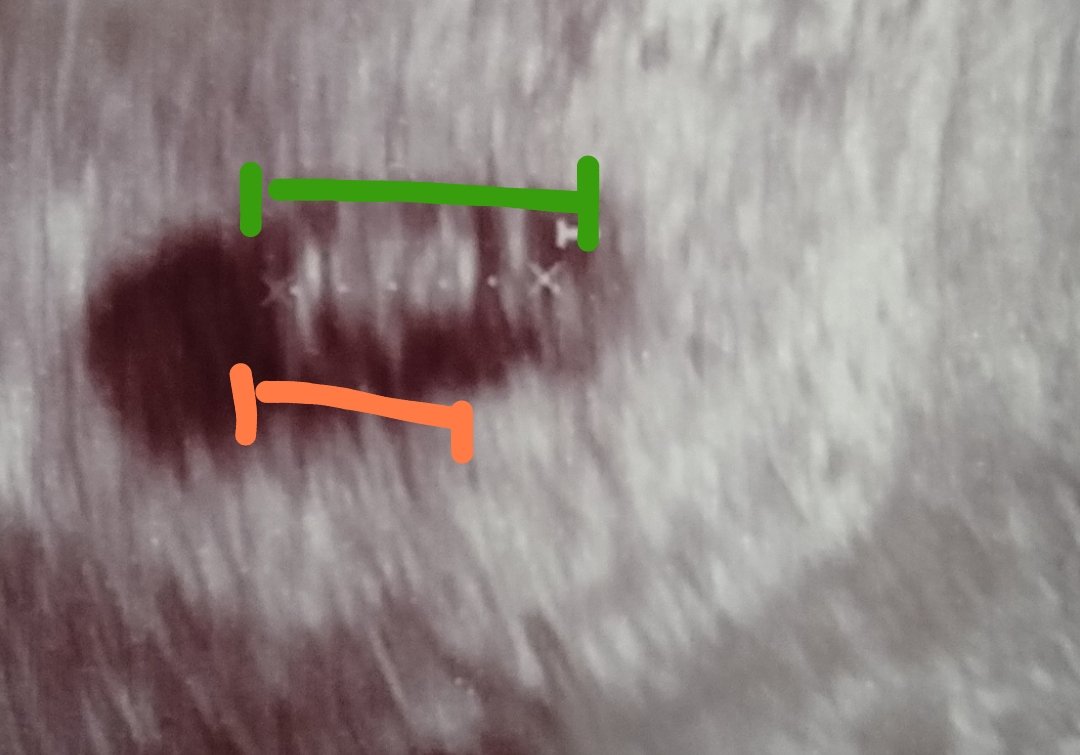

Příjde mi, že oranžová čára je délka plodu a zelená je délka plodu i se žloutkovým váčkem ( myslím, že jej vidím vpravo oddělen od plodu, trochu to tam jde vidět).

Vidíš tu přerušovanou čáru mezi dvěma křížky? Tam právě měří lékař délku tvého miminka.

@anonym_autor zhruba takto zatím